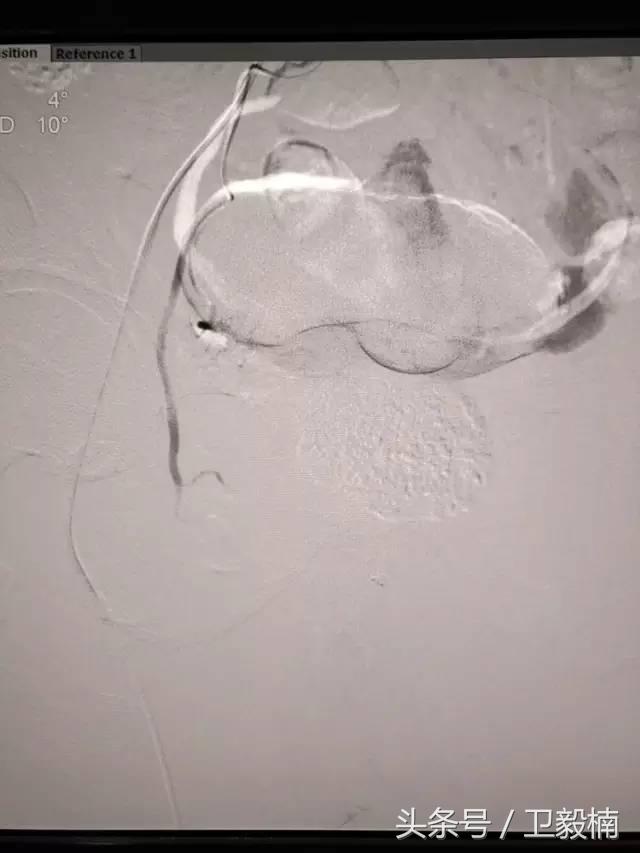

五、出血性疾病:鼻腔大出血、咯血、上消化道大出血、经皮肾镜术后出血、膀胱出血、产后出血等

2、经导管血管栓塞法(Transcatheter embolization)

经原血管造影的导管或特制的导管,将栓塞物送至靶血管内,一是治疗内出血如外伤性脏器出血、溃疡病、肿瘤或原因未明的脏器出血。另一是用栓塞法治疗肿瘤,因肿瘤循环部分或全部被栓塞物阻断,以达控制肿瘤之生长,或作为手术切除的一种治疗手段;亦可用于非手术脏器切除,例如注射栓塞物质于脾动脉分支内,即部分性脾栓塞,以治疗脾功亢进,同时不影响脾脏的免疫功能。

常用的栓塞物质如自体血凝块、明胶海绵、无水酒精、聚乙烯醇、液体硅酮、不锈钢圈、金属或塑料小球及中药白芨等。

(3)应用栓塞材料,钢圈,内支架治疗动脉瘤、AVM、动静脉瘘,血管性出血。